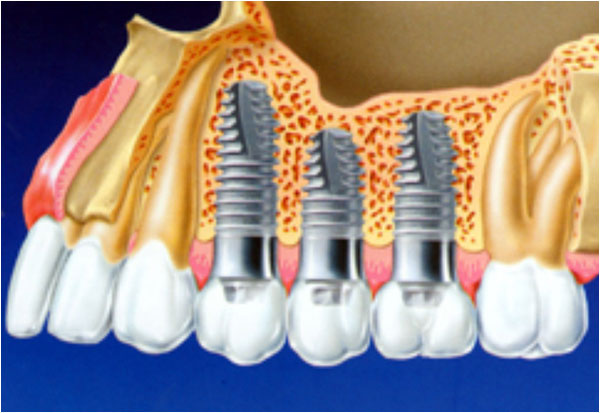

К всеобщему счастью сегодня существует предостаточно способов решения этой проблемы. Неоценимую помощь предоставляет возможность протезирования зубов. Протез: для многих — это слово может показаться не очень приятным и навеивать неприятные, и даже болезненные ассоциации. Но мы смело заверяем: профессионализм наших специалистов и высокое качество используемых материалов развеет все Ваши сомнения. Есть много разных способов и новых технологий протезирования зубов.

Другой современный вариант протезирования — Культевая вкладка. Она представляет из себя своеобразную конструкцию, изготовленную из слепка. Закрепляется конструкция при содействии специального цементирующего состава. Вставляя вкладку в обработанное заранее отверстие, стоматолог наращивает стенки и коронку. Разница между данной вкладкой и штифтом в том, что она не устанавливается за один прием. Но при этом она несет в себе гарантию качественной носки без выпадения. Такой зуб прослужит клиенту до конца жизни, а не выпадет после окончания гарантированного срока эксплуатации, как это бывает со штифтом.